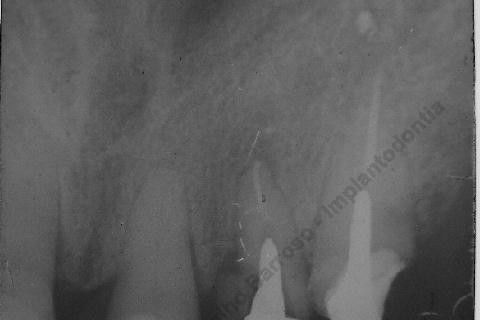

Inicalmente estava planejado um implante cone morse 3.5 X 15,0 EX, mas resolvi experimentar um implante HI oferecido pelo vendedor da Bionnovation, como brinde (ele soube que estou preferindo o cone morse mas não trabalham com este sistema), e não consegui carga imediata neste implante. O travamento não foi satisfatório, ficou com um pouco mais de 20 N, menos de 25 N. Apesar desta ocorrência isto não significa que dará problema, apenas não fiz com carga imediata, aguardaremos 4 meses para a osseointegração.

Se o implante utilizado fosse o CM EX 3.5 X 15,0, além deste tipo de implante possuir característica autorosqueante, promovendo pelo seu design um melhor travamento, o seu comprimento de 15mm + 2mm infraósseo, conseguiríamos 6 mm de travamento em osso "virgem" (comprimento da raiz era de 11 mm) e travaria na cortical nasal. Mas este que usei, hexágono interno cônico, fica ao nível do rebordo; o maior que fabricam (comprimento de 15 mm), não apoiou em osso cortical e não é autorosqueante como o EX da Neodent.